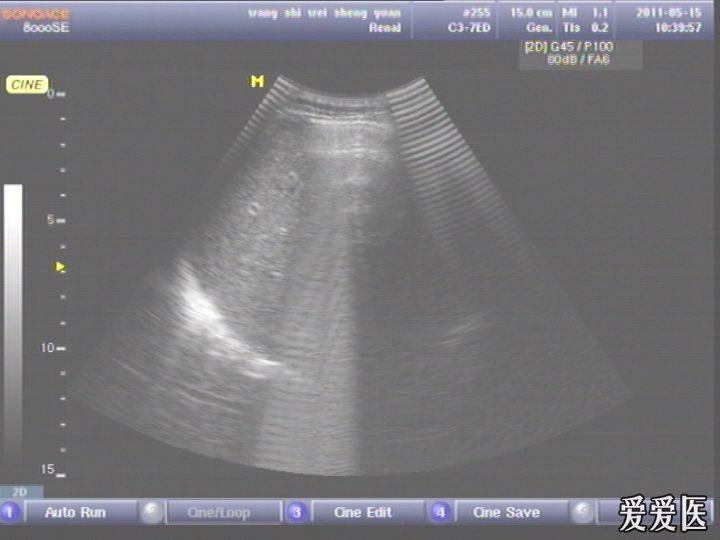

患者,男,38岁,进食后突发上腹部持续性剧烈疼痛一小时来查。超声见横膈与肝之间、上腹部皮下气体强反射回声,后伴多重反射,肝前、肝肾间隙,腹腔肠管间均可见游离无回声区。直视腹部见上腹部似板样。结合病史提示“胃肠道穿孔”。急诊手术证实。